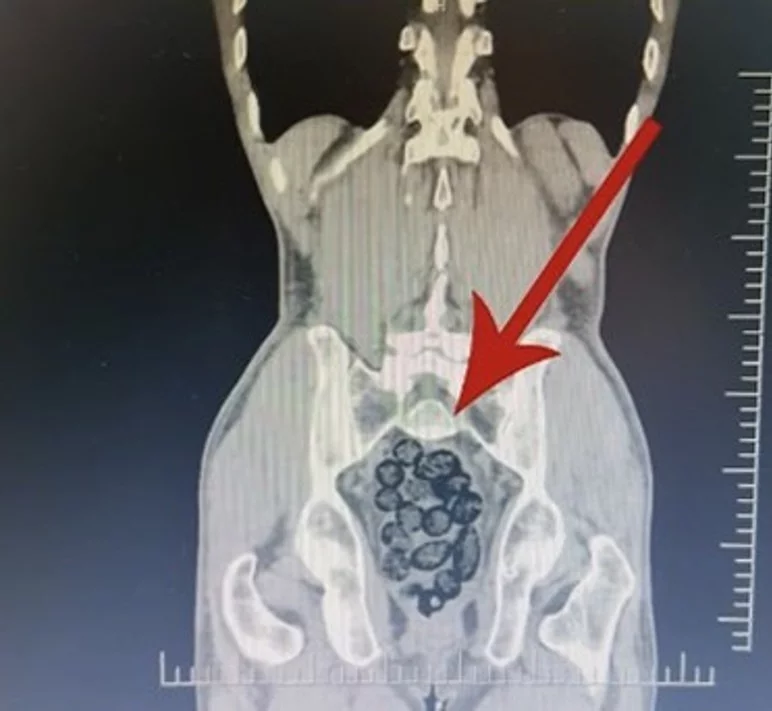

Durumundan şüphelenilen yabancı uyruklu bir yolcu üzerinde arama yapıldı. Yapılan incelemeler sonucunda yabancı uyruklu şahsın midesinde 64 Parça halinde toplam 472 gram uyuşturucu maddesi metamfetamin olduğu belirlendi.

Gözaltına alınan şahsın midesindeki uyuşturucu madde çıkartıldı. Emniyetteki işlemlerinin ardından adliye sevk edilen şahıs, çıkarıldığı mahkemece tutuklanarak cezaevine gönderildi.